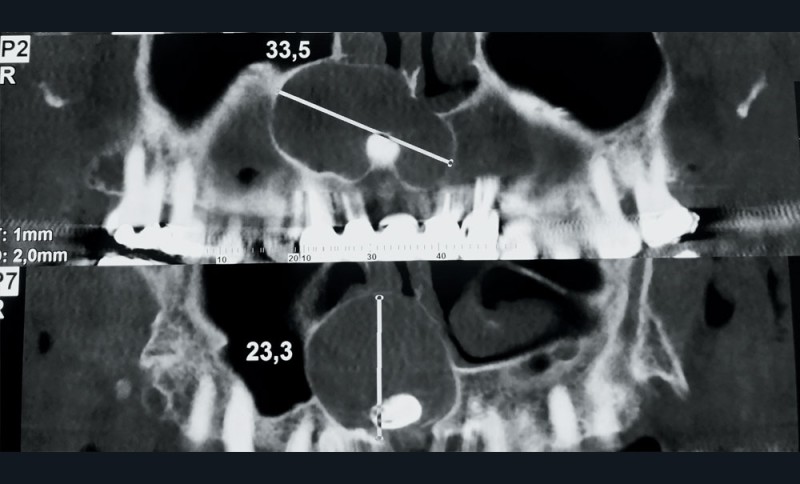

2. Le diagnostic de lésion kystique maxillaire étant posé, un examen tomodensitométrique est réalisé. Il met en évidence un volumineux kyste maxillaire antéro latéral droit (fig. 2 et 3).

Il existe :

a. une dent incluse

b. une lyse du plancher de la fosse nasale droite

c. une extension vers le sinus maxillaire droit

d. une lyse osseuse palatine